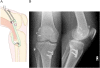

Background: Consensus has been lacking as to how to reconstruct the posterolateral corner (PLC) of the knee in patients with posterolateral instability. We describe a new reconstructive technique for PLC based on Larson's method, which reflects the physiological load-sharing pattern of the lateral collateral ligament (LCL) and popliteofibular ligament (PFL).

Findings: Semitendinosus graft is harvested, and one limb of the graft comprises PFL and the other comprises LCL. Femoral bone tunnels for the LCL and popliteus tendon are made at their anatomical insertions. Fibular bone tunnel is prepared from the anatomical insertion of the LCL to the proximal posteromedial portion of the fibular head, which corresponds to the insertion of the PFL. The graft end for popliteus tendon is delivered into the femoral bone tunnel and secured on the medial femoral condyle. The other end for LCL is passed through the fibular tunnel from posterior to anterior. While the knee is held in 90 of flexion, the graft is secured in the fibular tunnel using a 5 mm interference screw. Then, the LCL end is passed into the femoral bone tunnel and secured at the knee in extension.

Conclusions: Differential tension patterns between LCL and PFL is critical when securing these graft limbs. Intrafibular fixation of the graft using a small interference screw allows us to secure these two graft limbs independently with intended tension at the intended flexion angle of the knee.